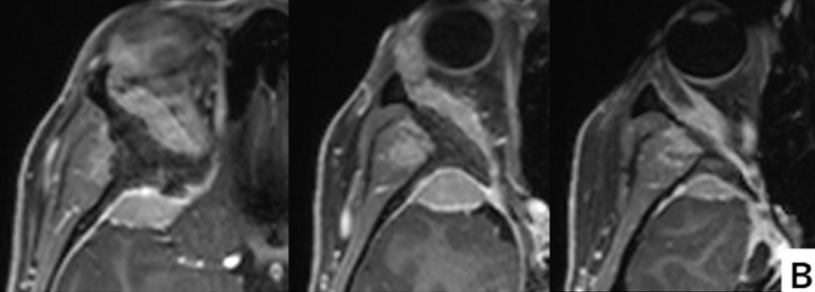

术前计算机断层扫描(骨窗)显示蝶骨大翼、蝶骨小翼、前床突及眼眶上壁、颞骨鳞部存在增生性改变。增强MRI检查可见蝶眶脑膜瘤从眶上壁延伸至外侧眶壁及眶周区域,颞极硬膜和颞肌受浸润,眼眶受压导致眼球突出征象。